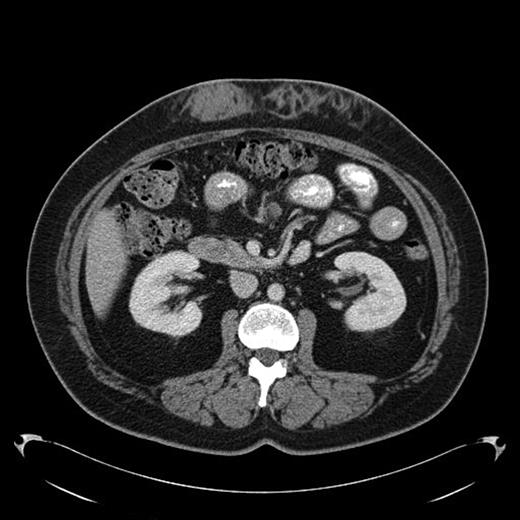

A 43-year-old female diagnosed with diabetes mellitus in 1986 after acute pancreatitis secondary to hypertriglyceridemia presented to our hospital in December of 2008 with a 2 year history of low grade fever of 99-100F. This was associated with chills and fatigue. Over the same time period she had noticed anterior abdominal wall nodularity, particularly at sites where she has been injecting her insulin. Her insulin requirement had also increased from a total of 60 units of NPH in a day to 170 units per day. Because of the subcutaneous nodularity at the site of injection a decision was made to switch the site of the insulin which resulted in lower blood glucose level and subsequently significant decrease in her insulin requirement to 120 units a day. This suggested poor absorption from the infiltrated site. At our clinic laboratory data showed normal white count of 5.4 × 10(9)/L with normal differential, normal hemoglobin of 12.9 g/dL with an ESR of 11 mm/hour, creatinine of 0.8 mg/dL and C-reactive protein of less than 3. As part of the work up for fever of unknown origin a CT-scan of the abdomen was obtained which showed infiltrative lesion in the anterior abdominal subcutaneous tissue with few calcifications Fig 1 & 2. Biopsy of the anterior abdominal wall nodular infiltrate was performed. Tissue cultures came out negative for infection. The biopsy showed eosinophilic material positive with Congo red staining and showing apple green birefringence when viewed under polarized light. Immunohistochemical staining showed this to be negative for AA, AL, or TTR amyloidosis. Liquid chromatography tandem mass spectrometry (LC MS/MS) detected peptides representing apolipoprotein E, apolipoprotein A-IV, SAP and Insulin. The amyloid deposits stained positive with anti-insulin. The presence of peptides from insulin and immunohistochemical reactivity with an anti-insulin antibody indicated that the amyloid deposits were caused by insulin injection at this site. Work up for systemic amyloidosis including serum protein electrophoresis with immunofixation was negative for a monoclonal protein. Quantitative immunoglobulins were within normal range. Her 24-hour urine protein was 65 mg within normal range. Her serum free light chains were unremarkable. Echocardiogram did not show any evidence of infiltrative cardiomyopathy. This was therefore consistent with localized insulin induced cutaneous amyloidosis. The recommendation was to change the insulin type and to rotate the insulin injection site. Because of occasional hemorrhage and pain the long term plan will be to surgically remove the amyloid deposits.

Fig 1.

Amyloid infiltration in subcutaneous tissue of upper abdomen at insulin injection site